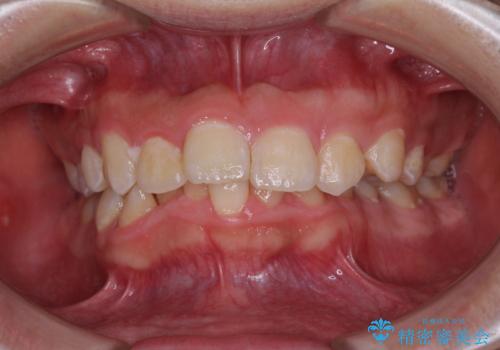

最新の症例